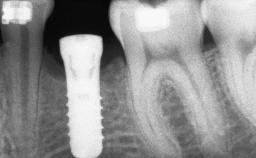

Ridge Preservation and Implant Placement for a Fixed Dental Prosthesis After a Car Accident

It is well known to clinicians that any removal of teeth will, over time, cause the dimensions of the alveolar ridge to be reduced by resorption of the bundle bone and by changes related to external modeling. This development is particularly evident in the crestal region with its thin buccal bone that consists of bundle bone almost entirely. The facial bone will rapidly resorb as blood supply from the periodontal ligament gets disrupted (Araújo and Lindhe 2005). There is no reason why traumatic tooth loss should not have the same consequences. It takes more than achieving implant osseointegration for a treatment outcome to be considered successful. No deficiency of bone or soft tissue is acceptable when an ideal esthetic outcome is the goal. Several articles (Sanz and coworkers 2011; Vignoletti and coworkers 2011) have reported on techniques of improving the alveolar ridge for implant treatment, notably focusing on protecting tissues from resorption.

Bone Augmentation Horizontal|Simultaneous|Sinus Floor Elevation|Staged

Augmentation Materials Xenogenous|Membrane

Bone Volume Deficient vertically or deficient vertically AND horizontally